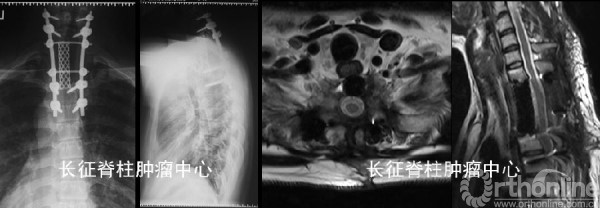

(1)导航辅助下后路胸1-3肿瘤En bloc切除重建内固定术

(2)术后处理:常规伤口换药引流、预防感染、支持治疗。病理报告:骨巨细胞瘤复发(初次手术病理不准确,可能与样本量小有关)。床上肢体功能锻炼,术后3周在支具保护下逐渐下地行走。

术后胸背疼痛症状缓解。行双磷酸盐治疗,术后1年随访未见肿瘤复发,内固定在位良好。